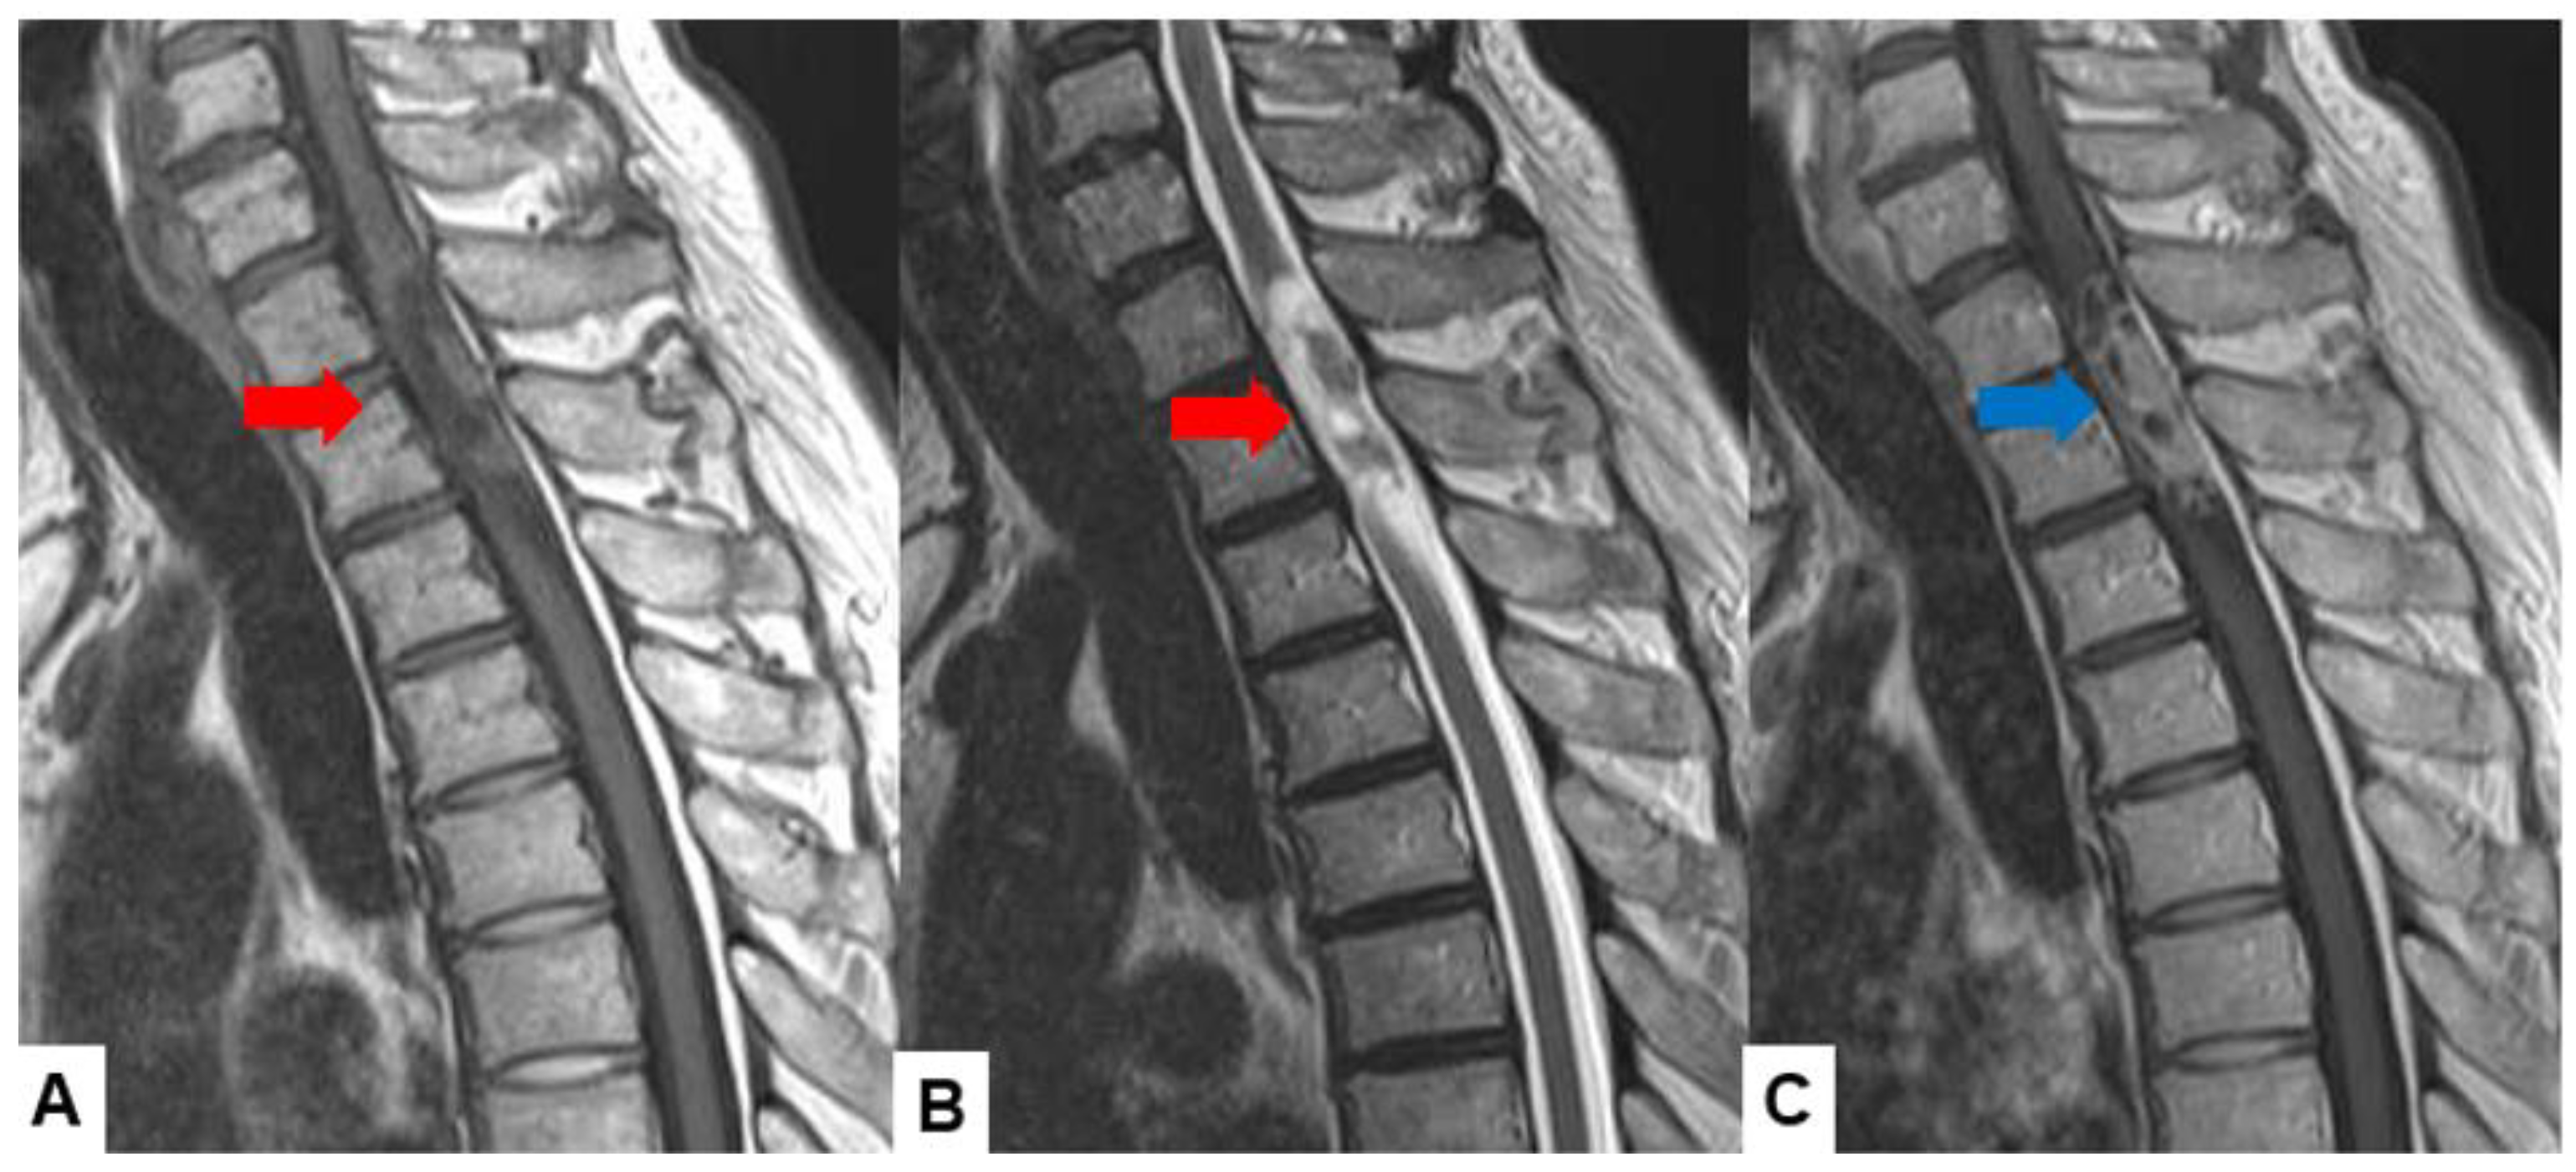

Schwannomas usually show low intensity in T1-weighted MR imaging and high intensity in T2-weighted MR imaging (Figure 1 and Figure 2). These tumors often enlarge alongside the nerve root and become a dumbbell-type [34]. The heterogenicity of a tumor indicates cystic change.

Figure 1.

Fifty-four M, spinal schwannoma. (A) T1-weighted midsagittal image, (B) T2-weighted midsagittal image, and (C) enhanced T1-weighted midsagittal image. Red arrows indicate tumor and blue arrow shows tumor enhancement. The tumor is mixed-intensity because of tumor necrosis.